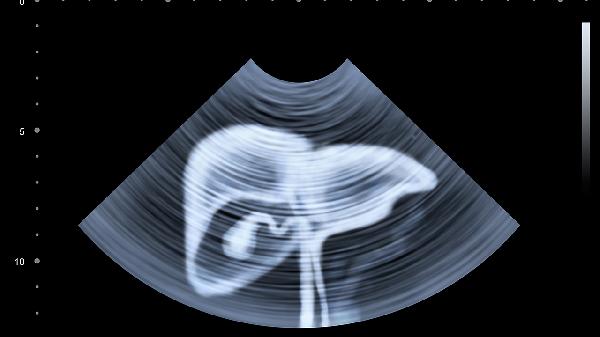

通過(guò)肝功能檢查、超聲等動(dòng)態(tài)評(píng)估恢復(fù)情況。膽紅素、轉(zhuǎn)氨酶水平變化反映肝細(xì)胞修復(fù)狀態(tài),凝血功能監(jiān)測(cè)合成能力。每1-3個(gè)月復(fù)查直至指標(biāo)穩(wěn)定,持續(xù)異常需調(diào)整治療方案。